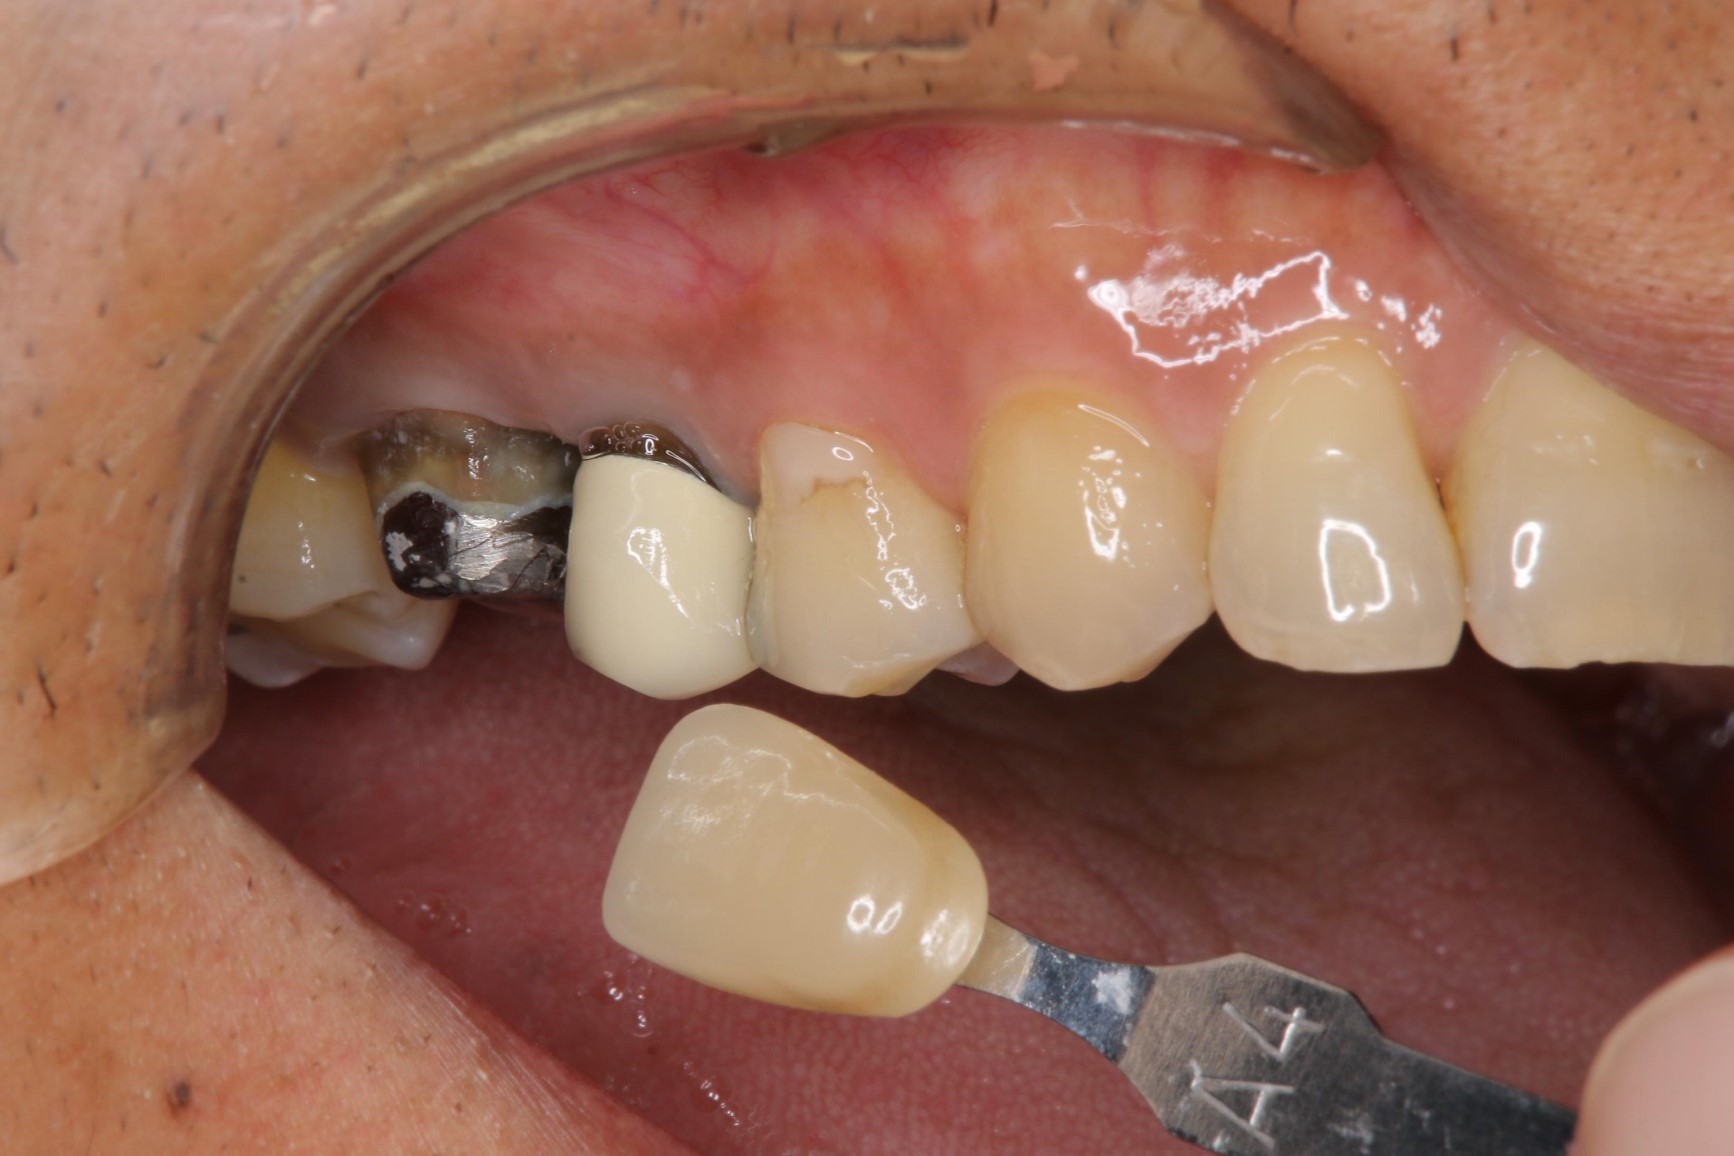

照相比色